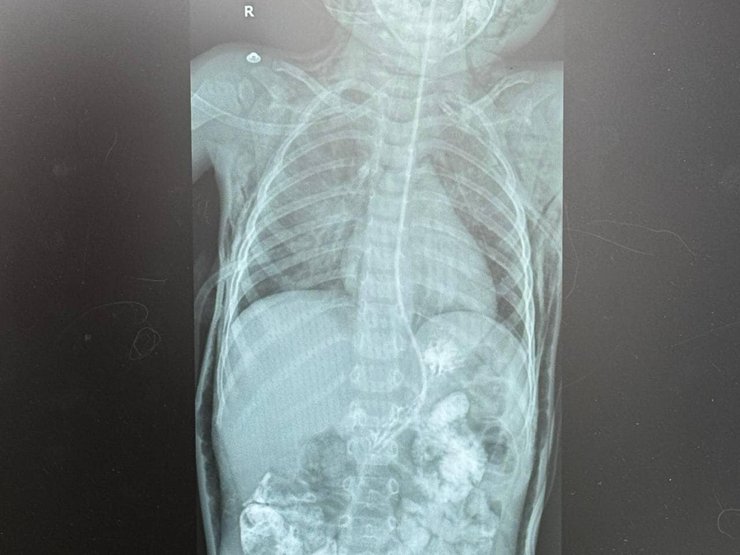

Медики провели рентгеновское обследование и КТ и обнаружили накопление воздуха в средостении, под кожей головы, шеи, грудной клетки. Это свидетельствовало о нарушенной целостности дыхательных путей у мальчика.

У мальчика произошел разрыв трахеи